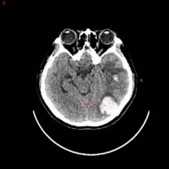

A 32-year-old woman in her 10th week of pregnancy presented to our hospital with nausea, vomiting and headache 10 days ago, increased nausea and vomiting with blurred vision and poor response 7 days ago, and yesterday developed a fever with a temperature of up to 38°C. She was admitted with a diagnosis of Wernicke’s encephalopathy combined with severe pregnancyrelated emesis. The patient had stopped menstruating 10 weeks earlier, denied oral contraceptive use, denied a family history of hereditary propensity to thrombosis, and denied a history of haematological disorders, autoimmune diseases, and intracranial and extracranial tumours. On admission, the patient’s main symptoms were persistent headache, nausea and vomiting, with normal vital signs and muscle strength. Her D-dimer level was 5.98 mg/L and β-human chorionic gonadotropin >10,000 IU/L. Other laboratory tests were essentially normal, such as routine blood, coagulation, urine, liver function, renal function and protein C. At the time of admission, the cranial CTV+CTA showed a tortuous left anterior cerebral artery segment A1, left jugular vein, left transverse sinus and sigmoid sinus thrombosis (Figure 1A), and cranial CT showed a large lamellar high-density shadow in the left temporal lobe surrounded by a lamellar low-density shadow. The diagnosis was venous sinus thrombosis combined with left temporal lobe cerebral haemorrhage (Figure 1B). He was admitted to the Intensive Care Unit(ICU) on a conservative basis, and a neurological consultation revealed poor mental health and limb weakness (4/5), with no other focal neurological deficits identified. After 3 days of conservative treatment, symptoms of drowsiness, blurred vision and impaired consciousness developed and CT showed an increase in the area of blood accumulation in the right ventricle (Figure 1C). An emergency mechanical thrombectomy was performed, after which the occluded left transverse and sigmoid sinuses were successfully recanalized and the haemorrhagic focus did not continue to increase in size (Figure 1D). Due to the presence of some residual thrombus, she continued postoperative LMWH therapy and urokinase thrombolysis, after which she was discharged in a stable condition with significant improvement in her symptoms. At the 1-month follow-up after discharge (Figure 1E), no recurrence of the disease was noted.

Figure 1A & 1B: Tortuous left anterior cerebral artery segment A1, left jugular vein, left transverse sinus and sigmoid sinus thrombosis.venous sinus thrombosis combined with left temporal lobe cerebral haemorrhage.